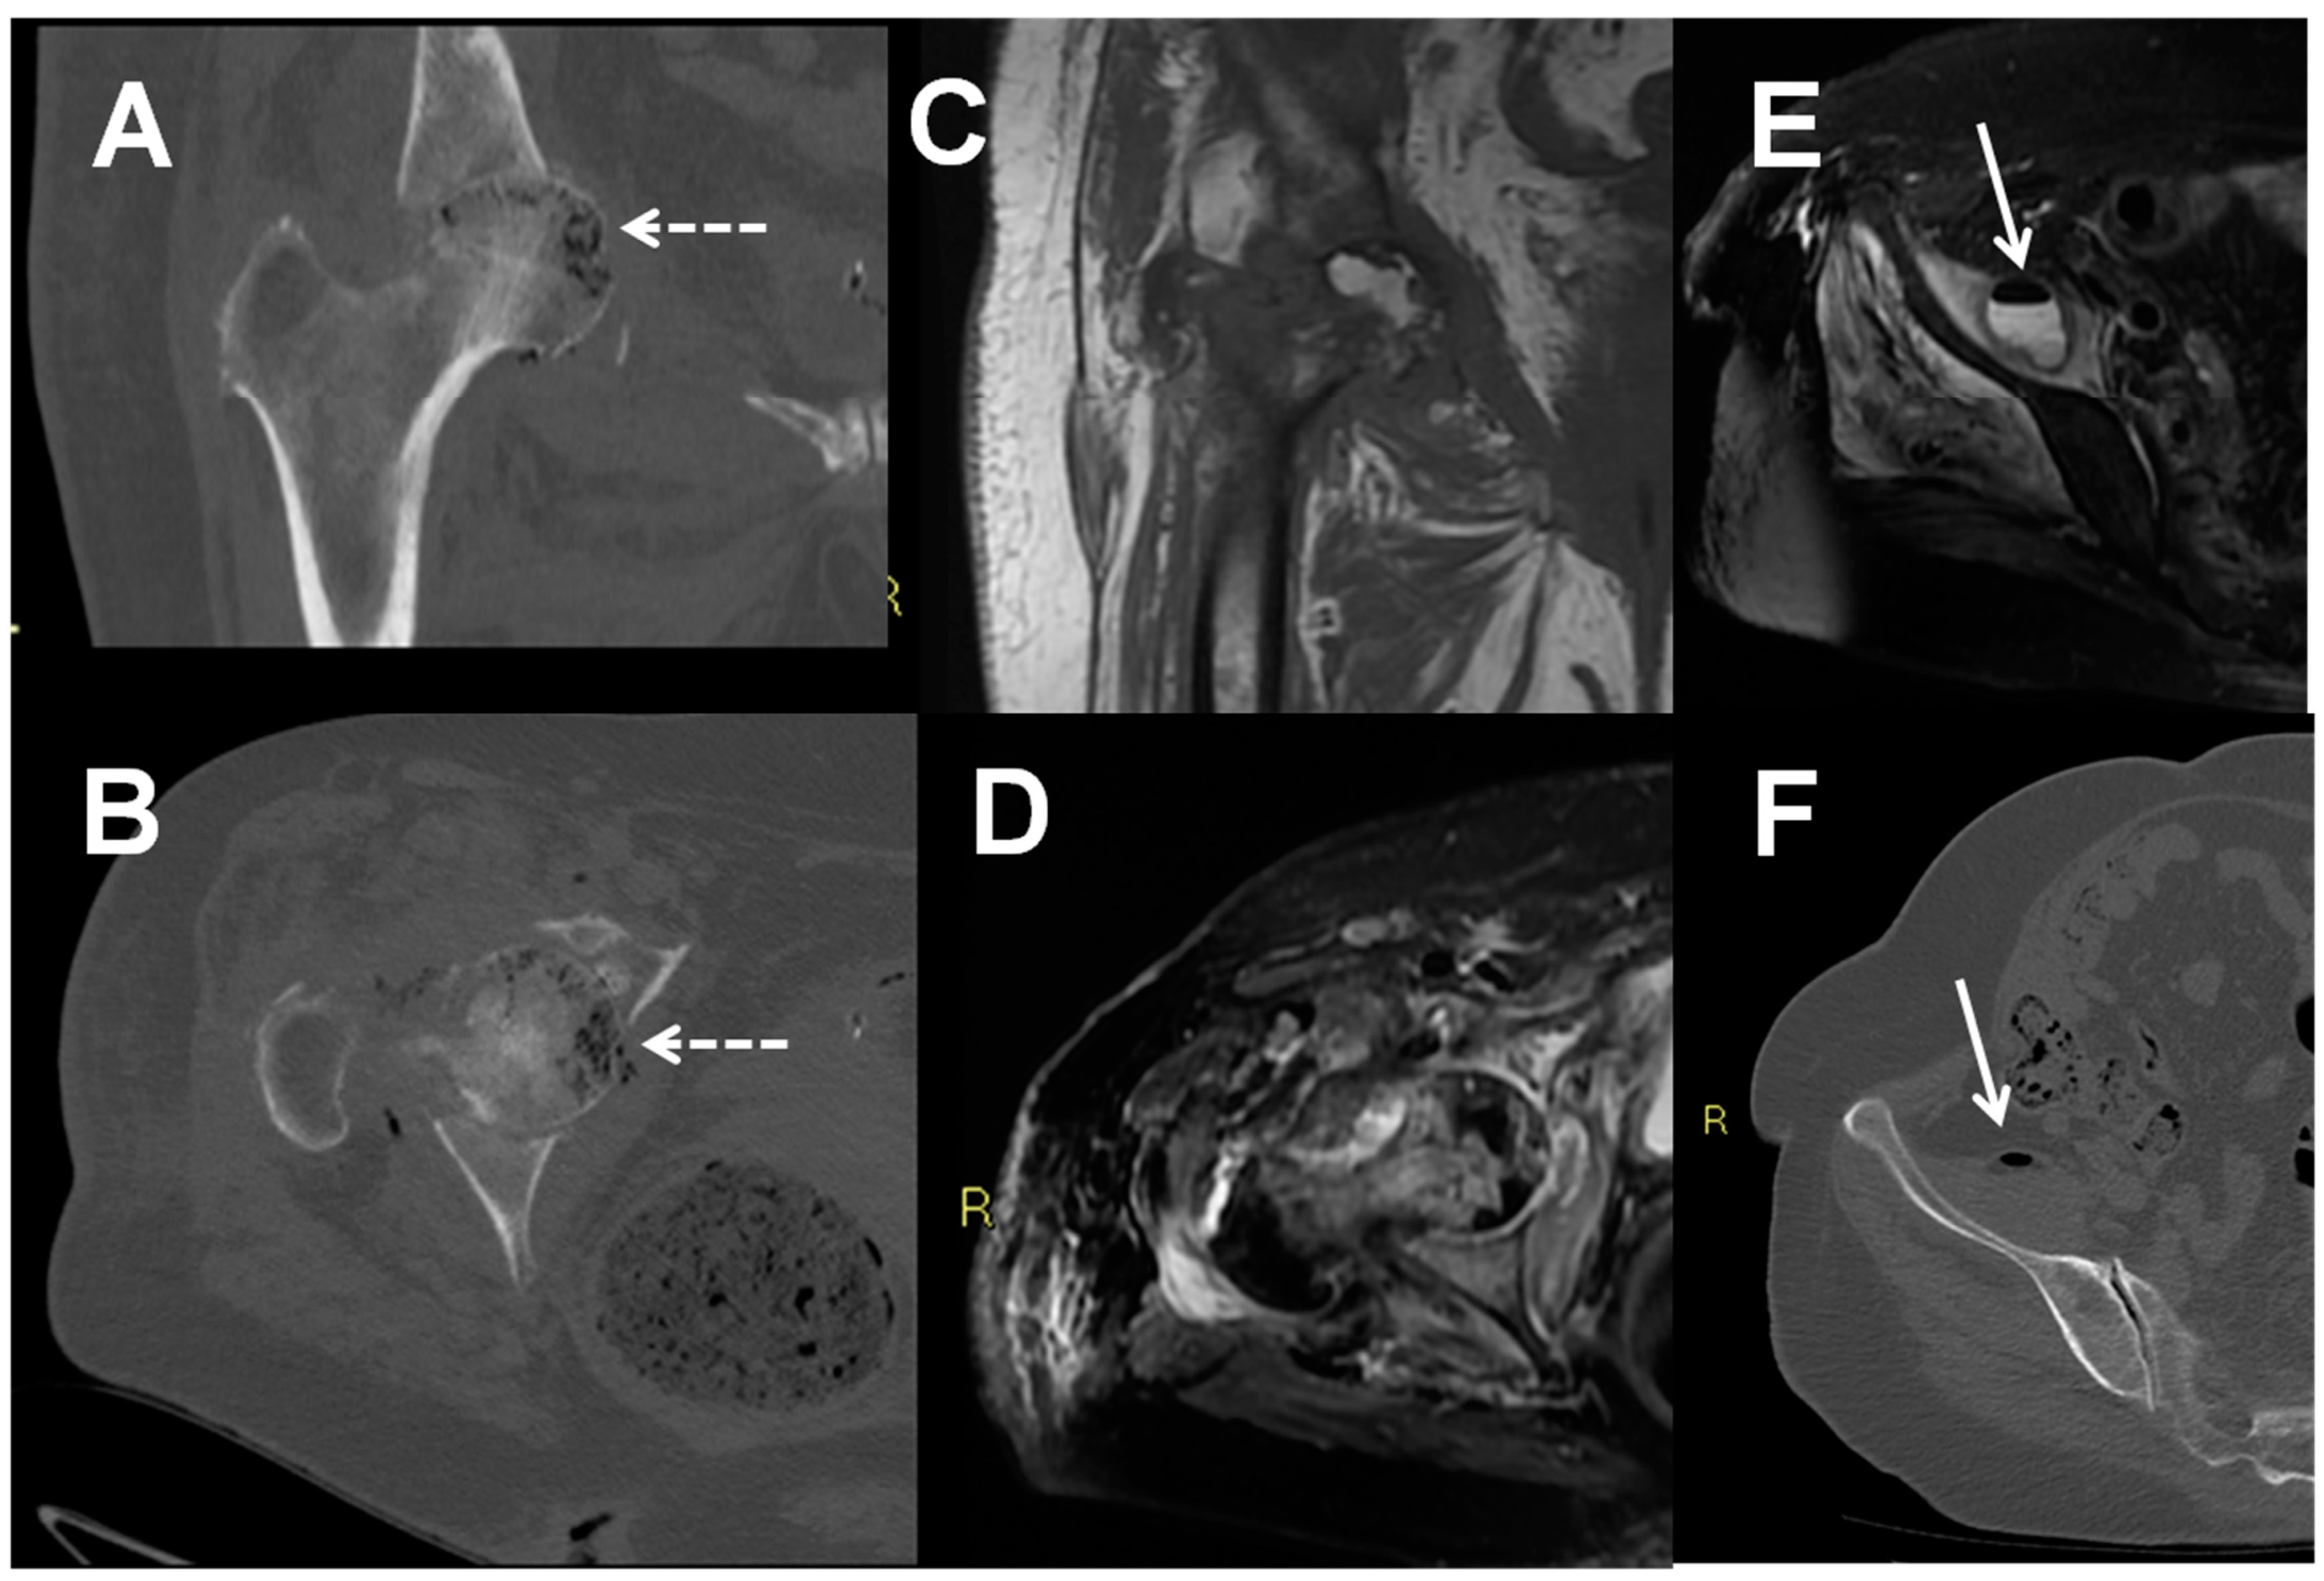

6. Diabetic Foot Osteomyelitis

- Signore, A.; Sconfienza, L.M.; Borens, O.; Glaudemans, A.W.J.M.; Cassar-Pullicino, V.; Trampuz, A.; Winkler, H.; Gheysens, O.; Vanhoenacker, F.M.H.M.; Petrosillo, N.; et al. Consensus document for the diagnosis of prosthetic joint infections: A joint paper by the EANM, EBJIS, and ESR (with ESCMID endorsement). Eur. J. Nucl. Med. Mol. Imaging 2019, 46, 971–988. [Google Scholar] [CrossRef] [Green Version]

- Isern-Kebschull, J.; Tomas, X.; García-Díez, A.I.; Morata, L.; Moya, I.; Ríos, J.; Soriano, A. Value of multidetector computed tomography for the differentiation of delayed aseptic and septic complications after total hip arthroplasty. Skeletal. Radiol. 2020, 49, 893–902. [Google Scholar] [CrossRef]